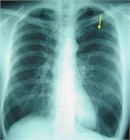

1. 患者のバイタルと胸部X線検査で肺虚脱度を確認し、バイタルの異常や虚脱の程度で治療方針を決定する。